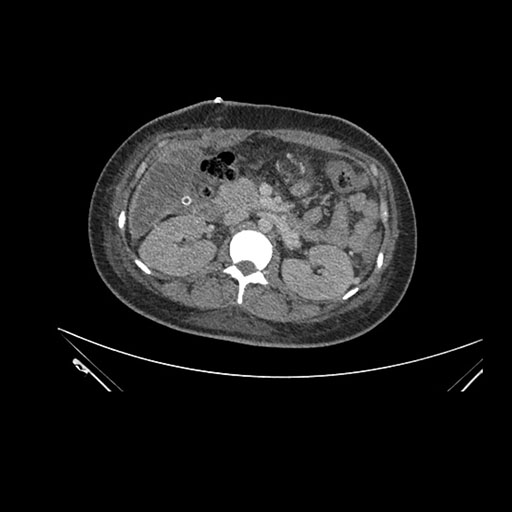

Axial Arterial